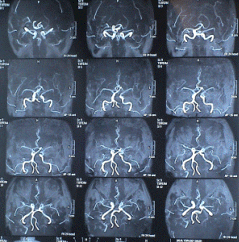

The patient was sent for another investigation. MRA showed complete occlusion of the left ICA and partial of the proximal segment of the ECA.

Check MRA performed 16-July-2006 showing the patency and established circulation 1 month after the operation.